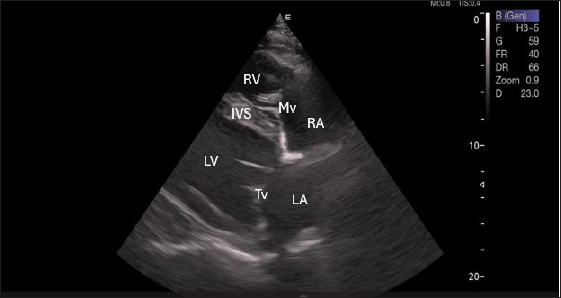

Right parasternal ultrasonography

By positioning the probe perpendicularly in the fourth intercostal space or longitudinally in the fifth space with a little clockwise rotation, the interventricular septum, ventricles, and atria could be observed in the caudal long-axis four-chamber view (Fig. 1). From this vantage point, all camels could be seen to have a left ventricle, mitral valve, interventricular septum, right ventricle, and tricuspid valve. Figure 2 shows that in the short-axis image of the cardiac ventricles obtained with a little clockwise rotation at the 4th ICS, only the right ventricle, interventricular septum, and left ventricle were visible. Here, the dimensions of all camel heart were measured in M mode. The right parasternal two-dimensional short-axis pictures of the heart’s base in the first frame were used to determine the LA/Ao ratio, by applying 2D and M mode (Figs. 3 and 4). Despite some difficulties, we successfully acquired a pulmonary image by attempting to acquire the right ventricular outflow tract for the right short axis at the level of the great vessels.

Fig. 1. Right parasternal longitudinal axis (systole) of 16 years racing camel showing Lv=left ventricle, Rv=right ventricle, Ivs=Inte3r ventricular septum, Mv=mitral valve, and Tv=tricuspid valve.